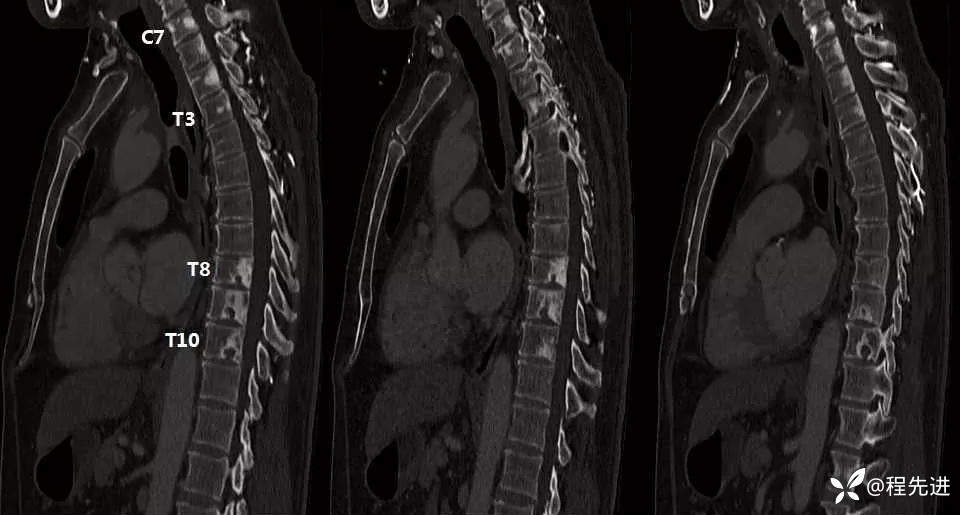

增强动脉期骨窗

增强动脉期骨窗矢状位(注意与上面平扫对比,并重点讨论!)

- C7-T3椎体病灶最可能的诊断是?

- T8-T10椎体病灶最可能的诊断是?